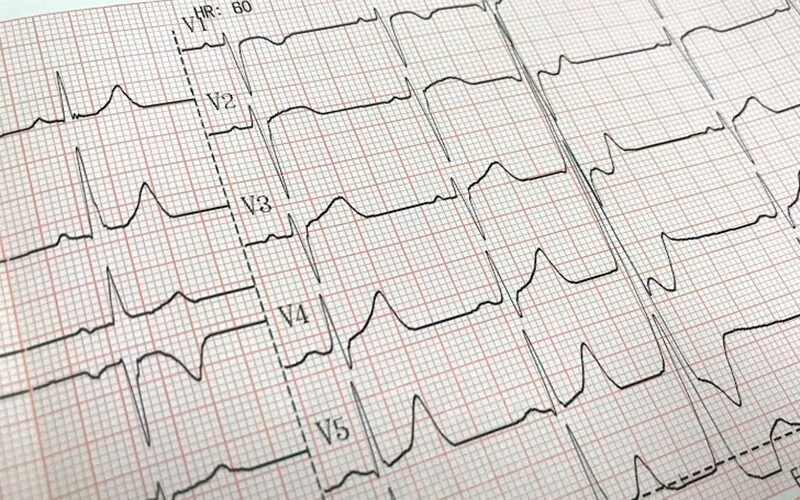

- 心臓の疾患

心不全などは、血液の流れが滞り、足を中心にむくみが出ることがあります。また、息切れや体重増加を伴うこともあります。 - 腎臓の疾患